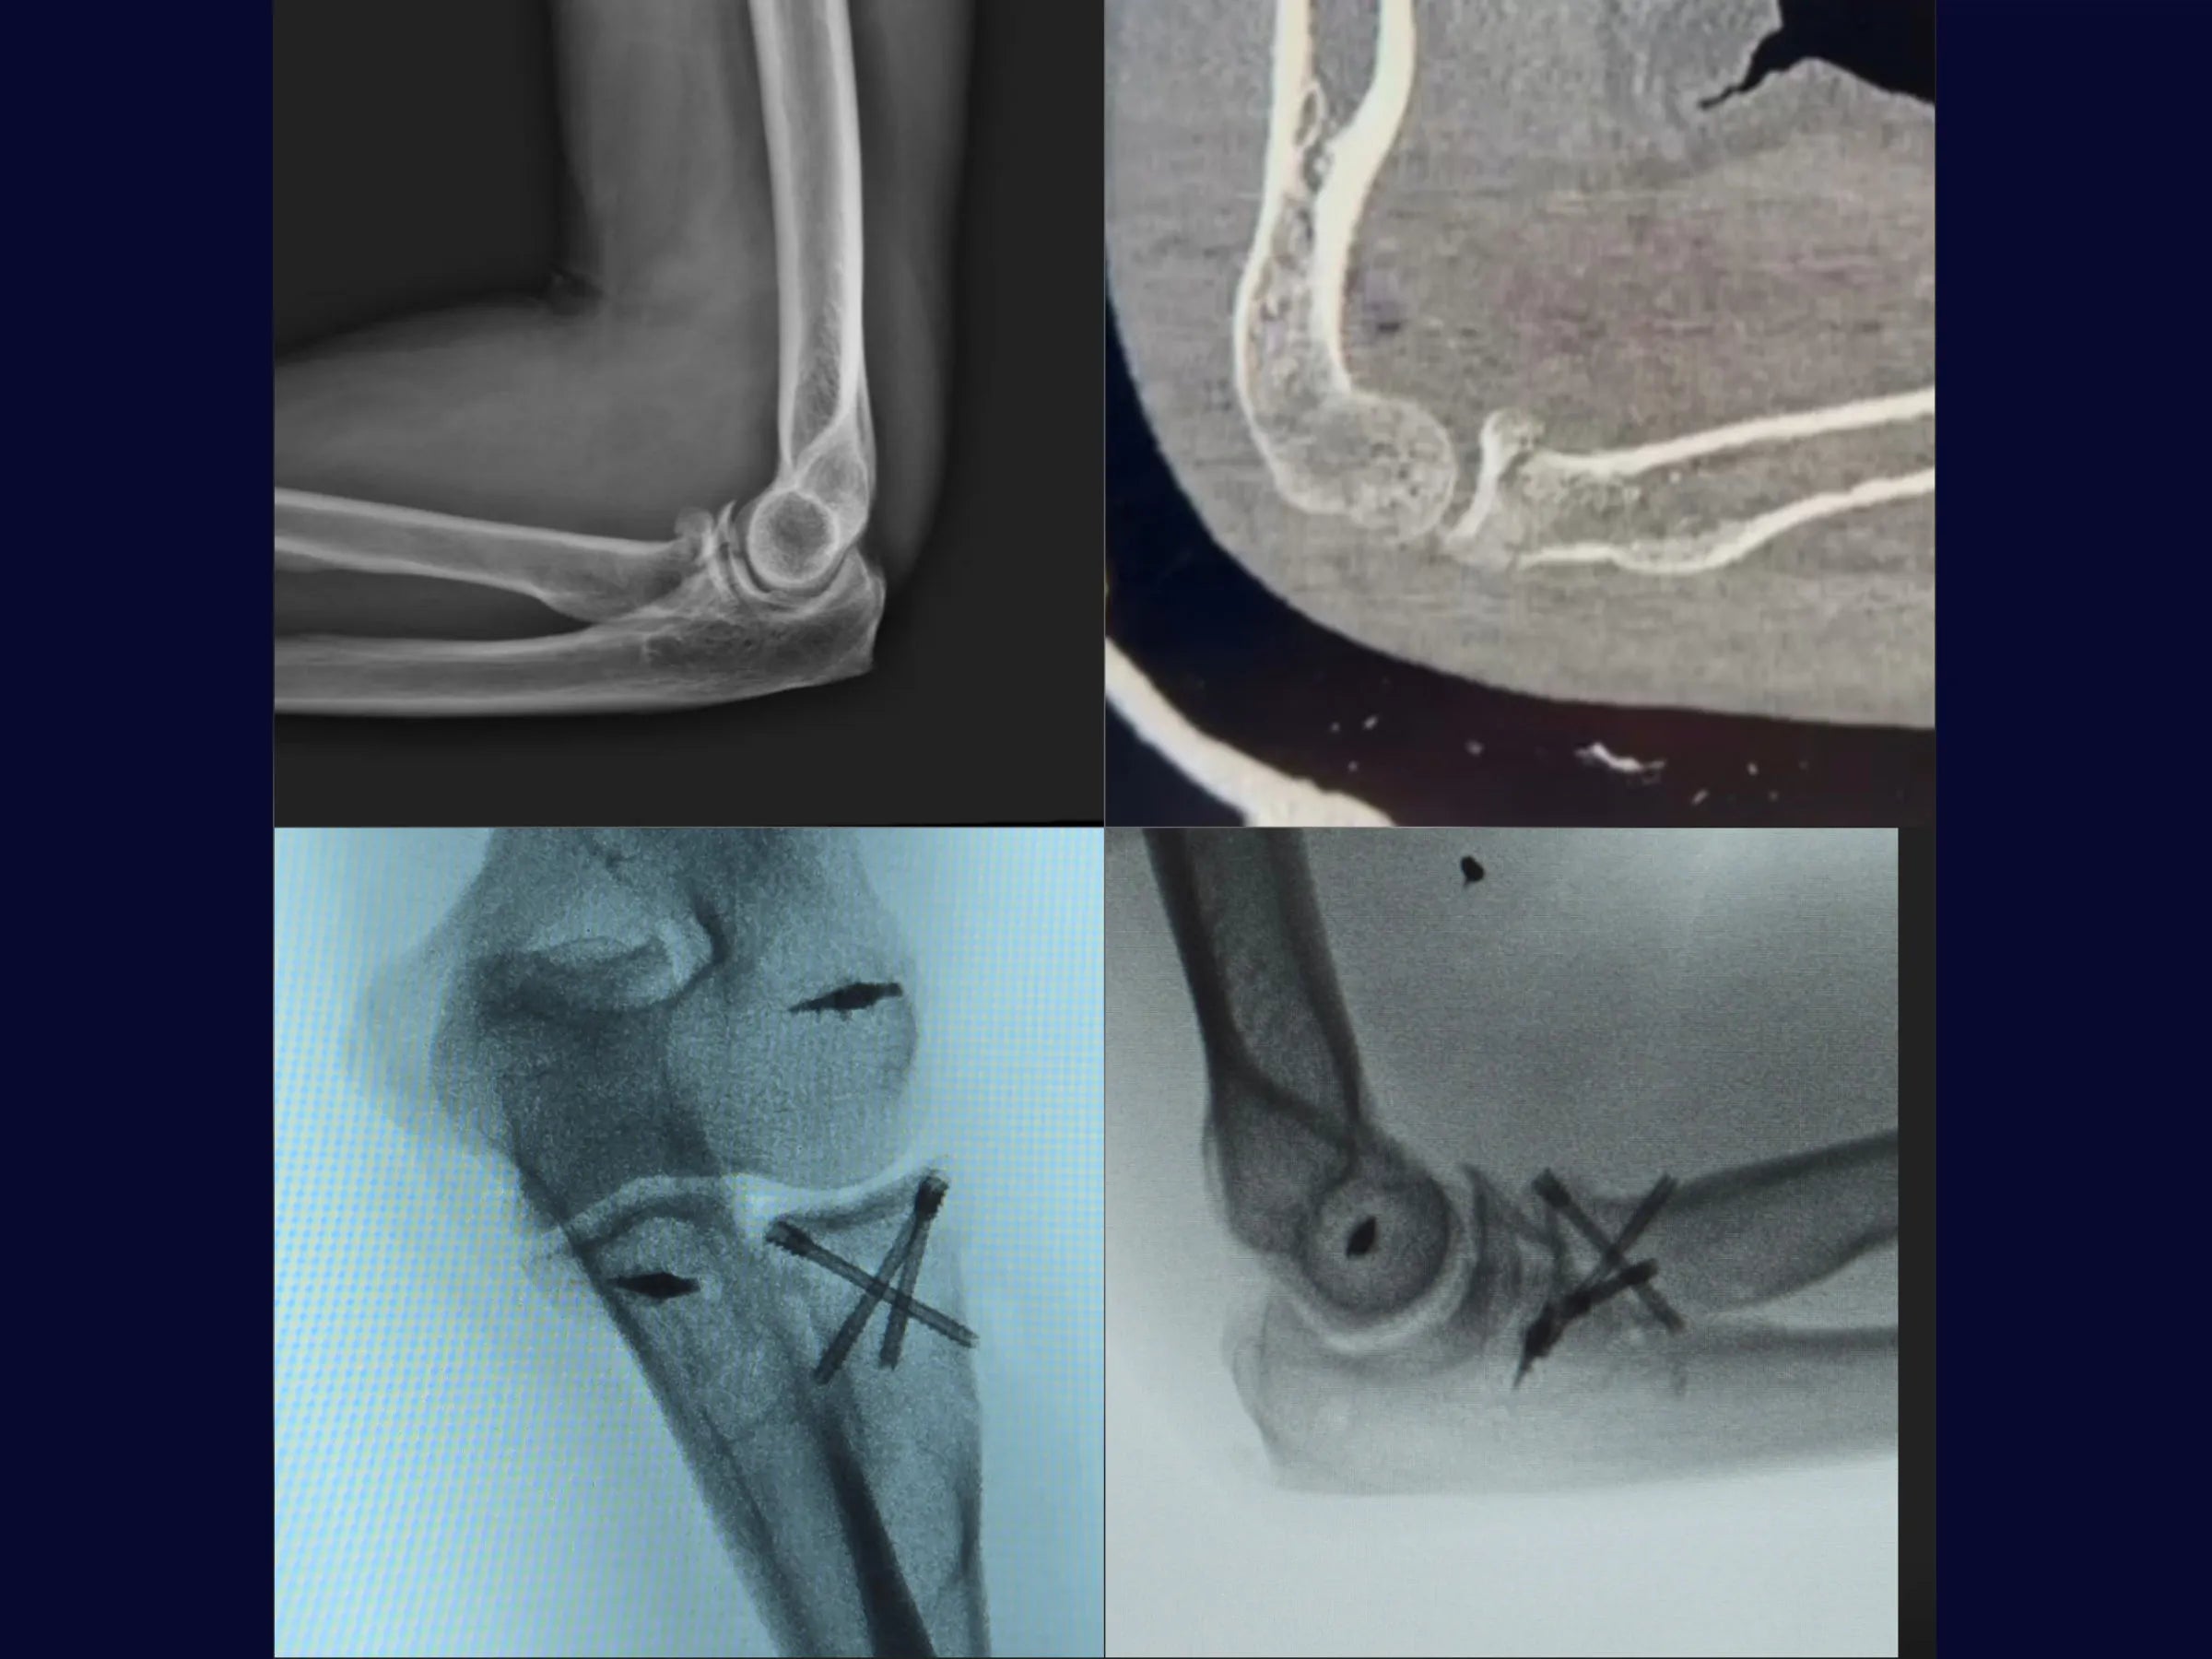

A instabilidade do cotovelo após fraturas da cabeça do rádio com avulsão do coronoide representa um desafio frequente.

Este treinamento apresenta a técnica do tripé com parafusos de dupla compressão e reinserção capsular com âncora metálica, em vídeo 4K sob a perspectiva cirúrgica, permitindo compreender cada detalhe técnico e aplicar com segurança na prática.

- Técnica do tripé com parafusos de dupla compressão (2,4 mm).

- Fixação Segura: Parafusos sepultados em ângulo biomecânico de 45°.